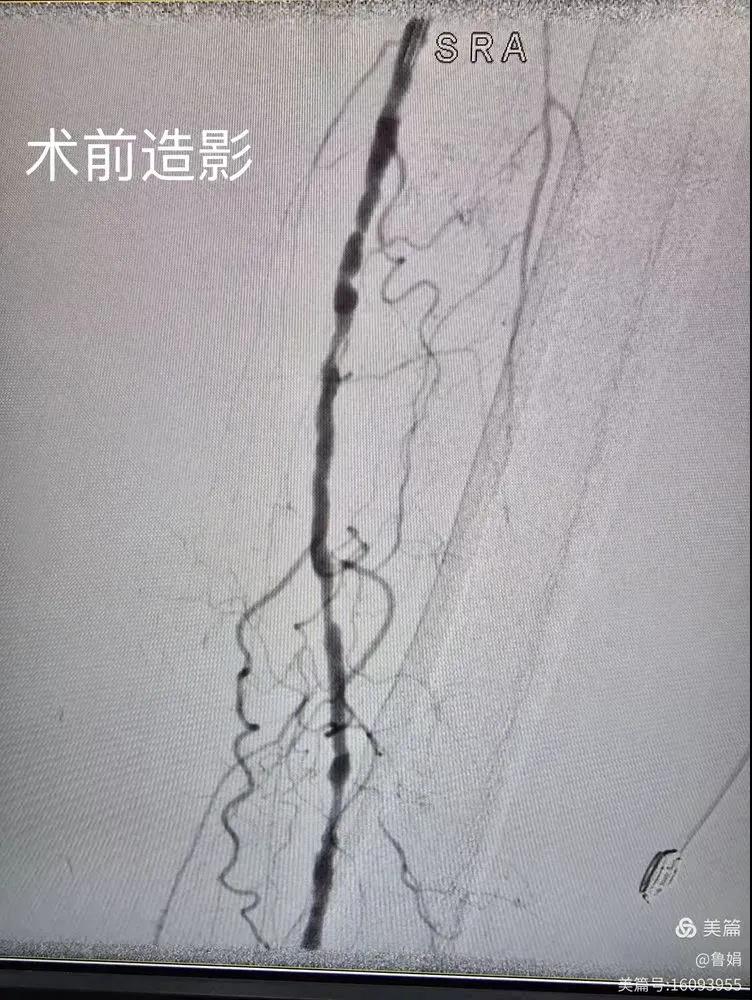

據(jù)悉,該患者,女,73歲,下肢動脈硬化閉塞癥,“以靜息痛,間歇性跛行”入院,CTA評估:股淺動脈,腘動脈間斷性多段重度狹窄,外二科血管外科團隊根據(jù)患者病情,結合檢查結果,經(jīng)過科室會診后,決定對該病人行介入治療。手術由周創(chuàng)業(yè)副主任與北大一院血管外科專家郭宏杰教授聯(lián)合開展,對股淺動脈,腘動脈重度閉塞段行血管開通+藥涂球囊擴張成形,術后狹窄明顯緩解,血流恢復!